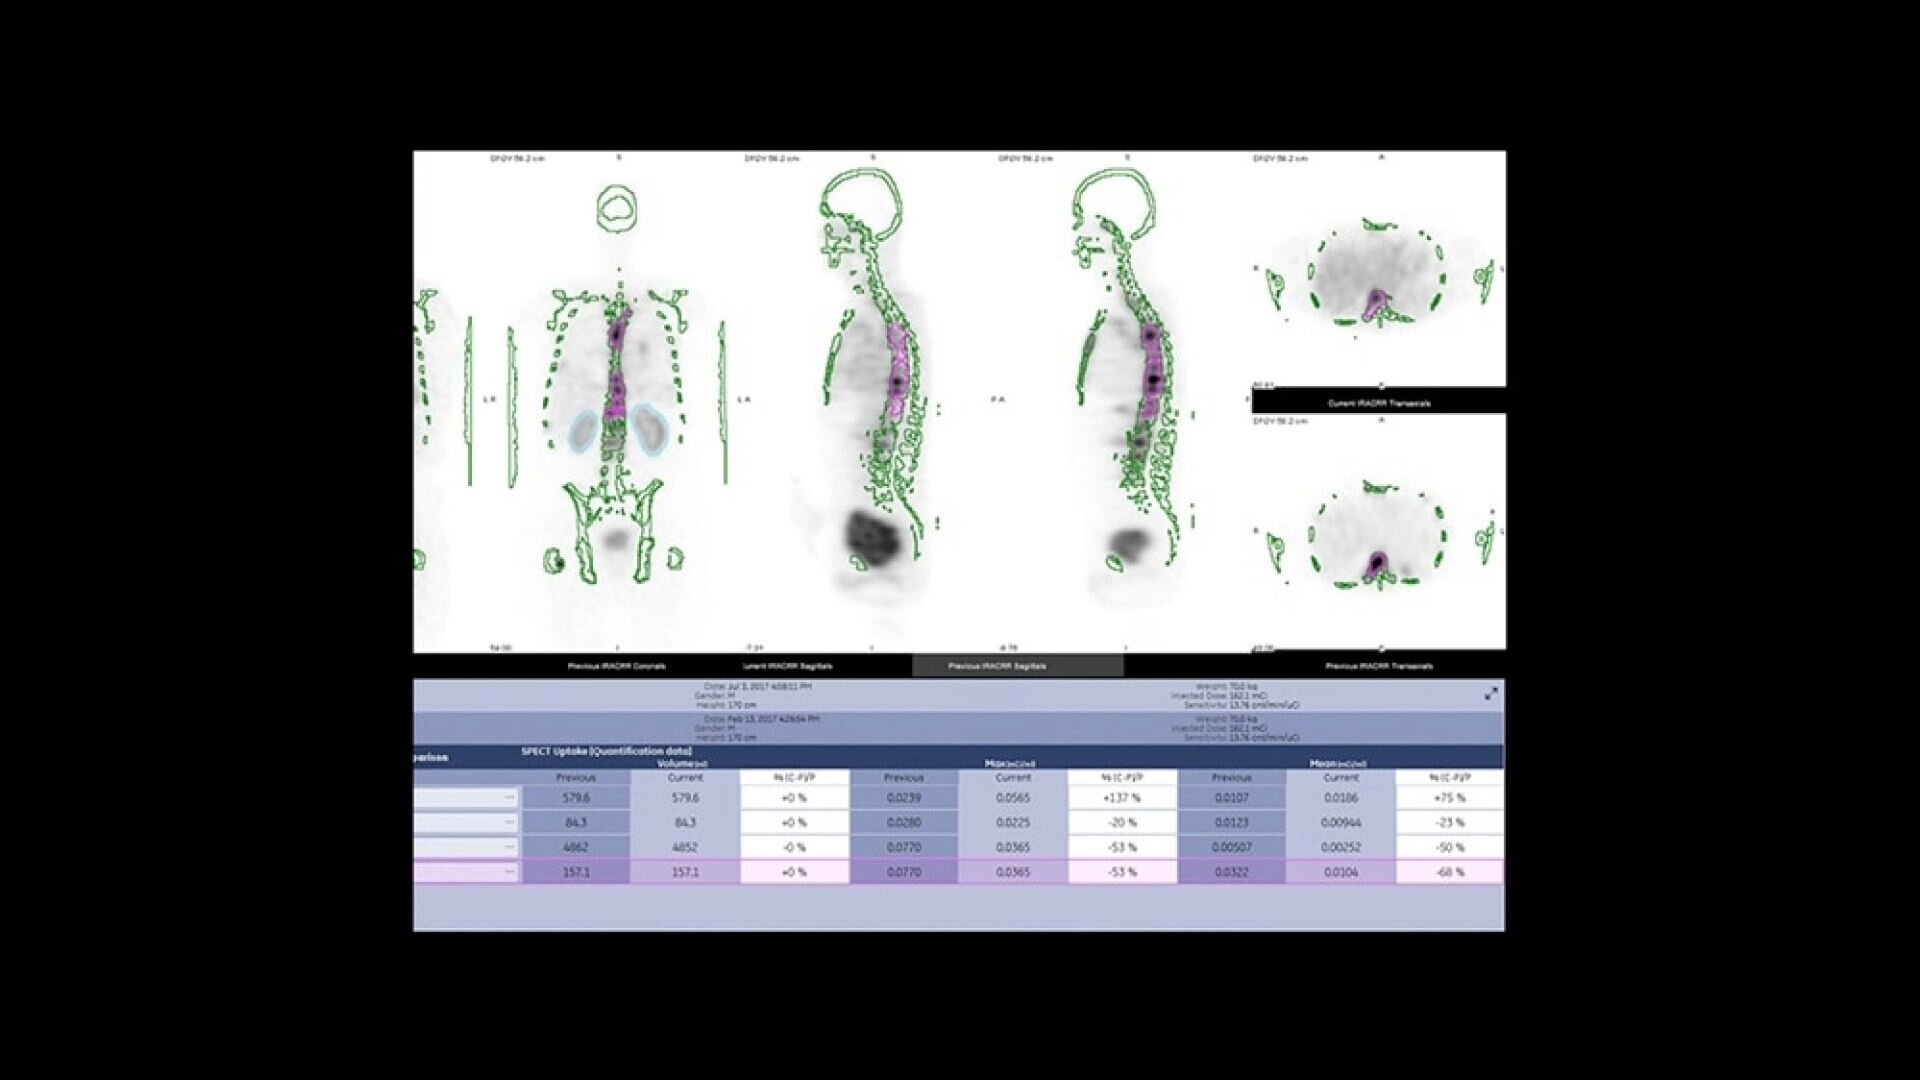

One home for all your molecular images

SmartConsole makes advanced procedures more accessible by transferring exams directly to the PACS or other pre-defined DICOM destinations with no operator intervention, even if SPECT/CT fusion is not supported, by exporting the studies in DICOM PET format. You can generate and send an additional dataset in PET DICOM format to enable quantitative SPECT results and SPECT SUV (Standard Uptake Value) on any PET DICOM compliant workstation or PACS. Referring physicians can review and evaluate your SPECT/CT exams with the same quality of information they have come to expect from your PET/CT, as adjunct information to the original SPECT/CT images.

nm-ct-870-czt-molecular-images-st-en